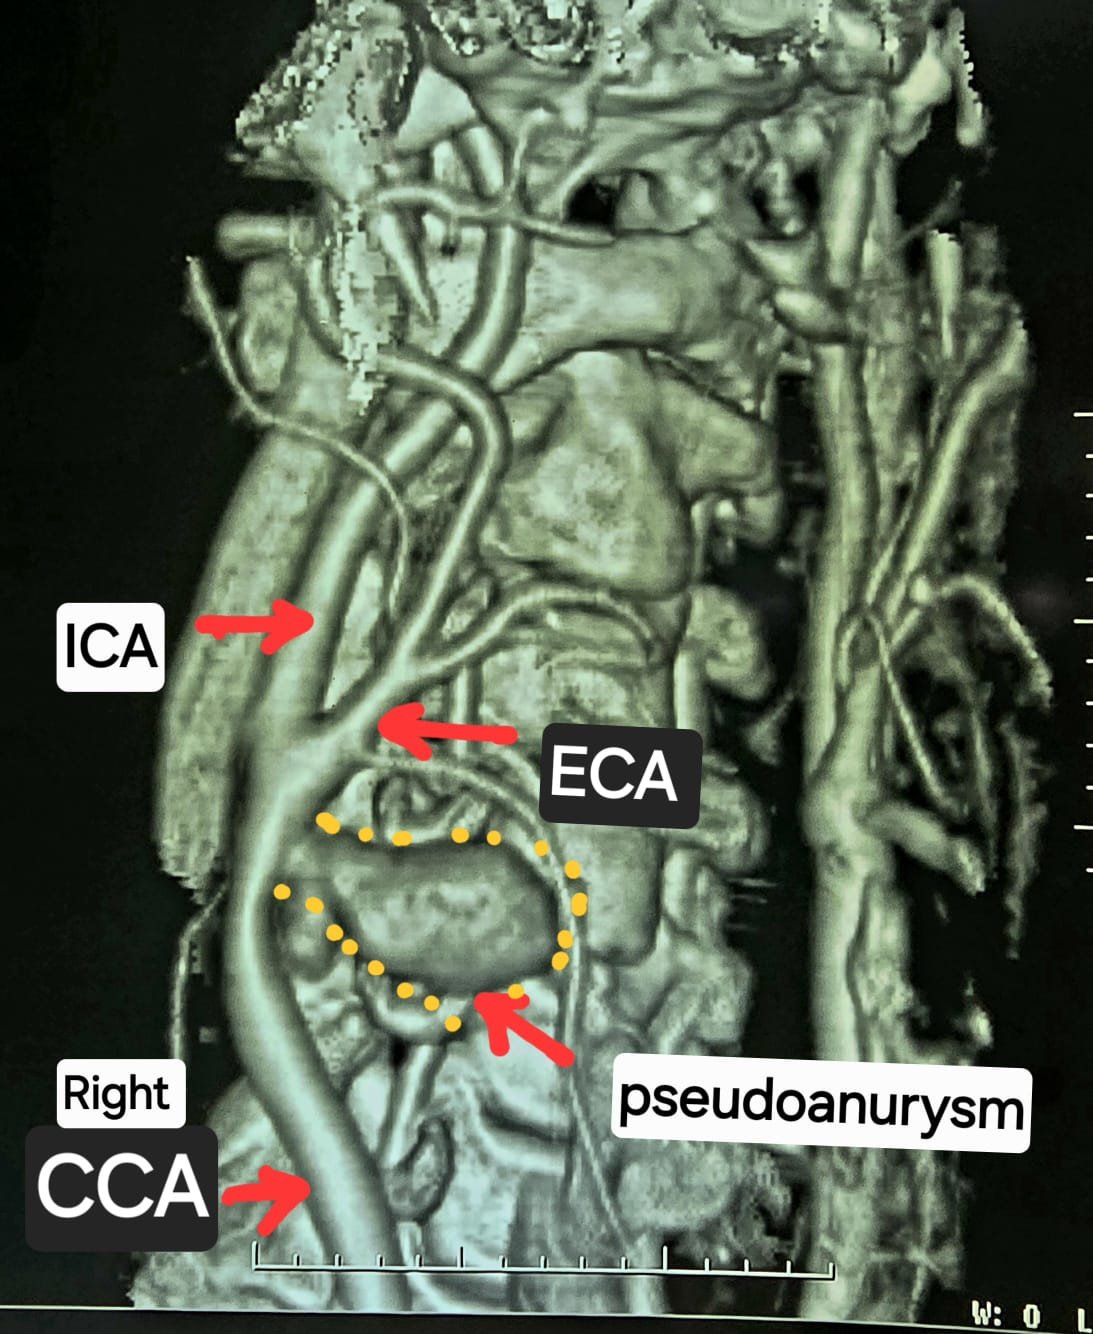

गर्दन के नसों की सीटी एंजियोग्राफी जांच में यह चौंकाने वाला तथ्य सामने आया कि मरीज की दायीं कैरोटिड आर्टरी फट चुकी है और उसके चारों ओर गुब्बारानुमा संरचना बन गई है, जिसे कैरोटिड आर्टरी स्यूडोएन्युरिज्म (Carotid Artery Pseudoaneurysm) कहा जाता है। स्थिति की गंभीरता को देखते हुए मरीज को तत्काल हार्ट, चेस्ट एवं वैस्कुलर सर्जरी विभाग में में डॉ कृष्ण कांत साहू के पास भेजा गया।